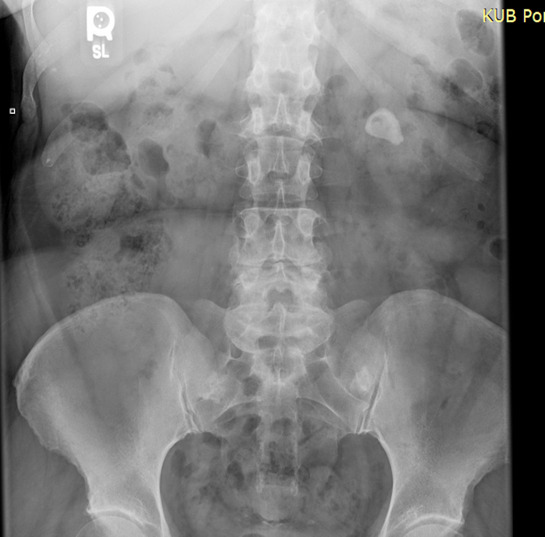

After the examination was performed, the patient was sent to the chiropractic clinic radiology department for a series of spinal views and a KUB radiograph. The KUB view (figure 1) showed a 2.6 cm (about 1.02 in) calcification within the left renal calculus.

The patient was referred to a urologist for an abdominal computerized tomography (CT) scan. revealing a 2.6 cm (about 1.02 in) stone in the upper pole of her left renal calyces. A urinalysis confirmed blood in the urine with high specific gravity. She was scheduled for surgery due to the size of the stone. Lithotripsy is an effective treatment suited for KSD under 2 cm, whereas stones that are larger than 2 cm (about 0.79 in) are candidates for surgery.16 The surgery removal determined the stone type was calcium oxalate. Following surgery, the patient reported no LBP, SJP or mid-thoracic pain.